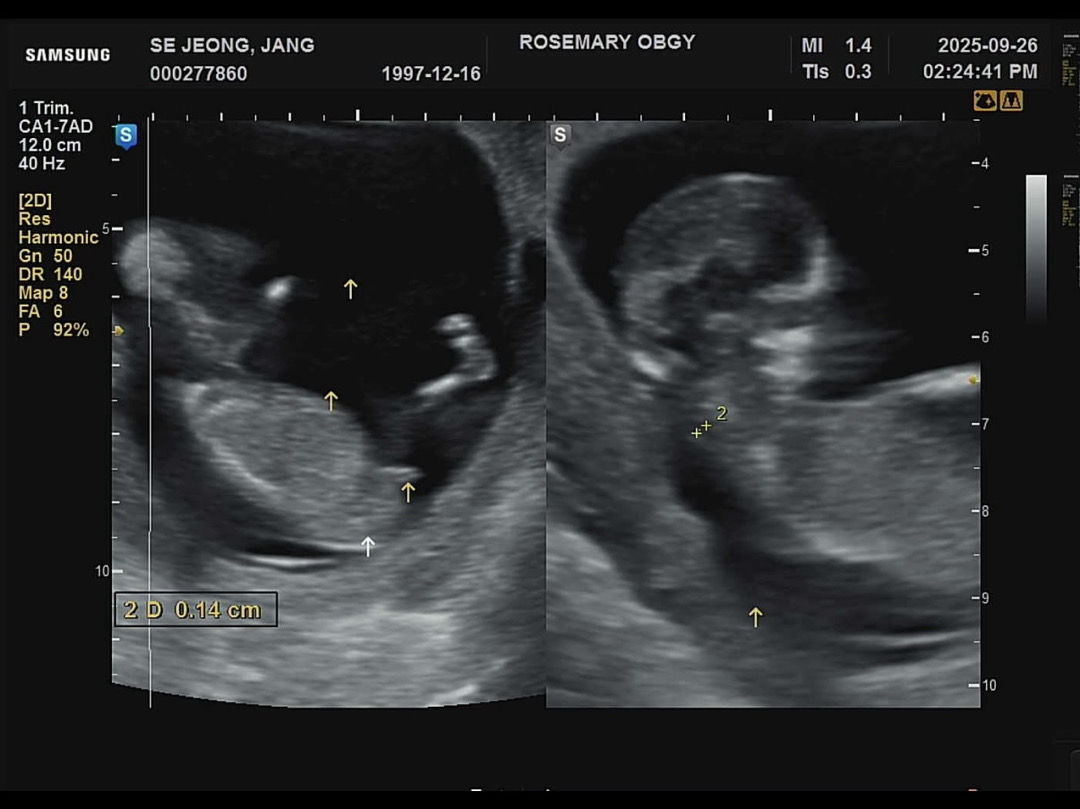

12주 각도법 판단해주세요

담당선생님께서는 아직 모르지만 딸같기도 하다는데 어때보여요???